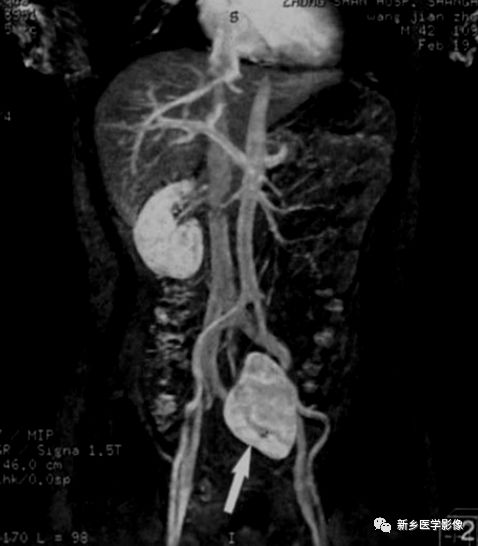

MR特点

双肾下极越过中线,以实质或纤维性连接。合并结石、积水可见不规则T1WI低、T2WI低或高信号,边缘清晰及扩大的肾盂。合并肿瘤可见不规则的T1WI低、T2WI低、高信号,合并出血或坏死可出现 明显T1WI低、T2WI低信号或高信号。冠状面可见拉长的下肾盏结构,可见到起源于主动脉较低水平的多支供血动脉及其他畸形。

马蹄肾是最常见的融合肾类型,不合并肾肿瘤或炎症等病变时,临床无症状。CT和MR可明确诊断。但需注意并发症的存在及血供情况。